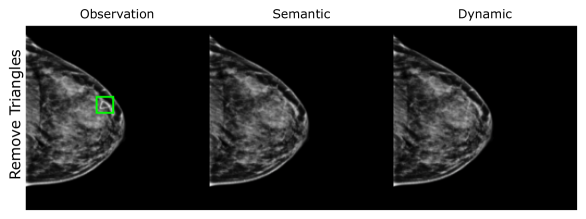

EMBED

Using prior insights, we apply our mechanisms to a real-world artefact removal task on the EMory BrEast imaging Dataset (EMBED) (Jeong et al., 2022). Schueppert et al. (2024) observe that triangular and circular skin markers are spuriously associated with breast cancer in classifiers due to shortcut learning (Geirhos et al., 2020), and manually labelled 22,012 affected mammograms. Using this dataset, we train a significantly scaled-up, amortised, anti-causally guided semantic mechanism () to remove skin markers. We model triangular markers (), circular markers (), breast density (), and cancer () as independent parents of the mammogram , and remove artefacts by intervening on and while holding and fixed. Figure 6 shows that our mechanisms effectively remove artefacts and can disentangle representations for triangles and circles. We successfully remove of triangles and of circles in our test set - a noteworthy result given the dataset’s small size and the scarcity of labelled skin markers (Appendix I).